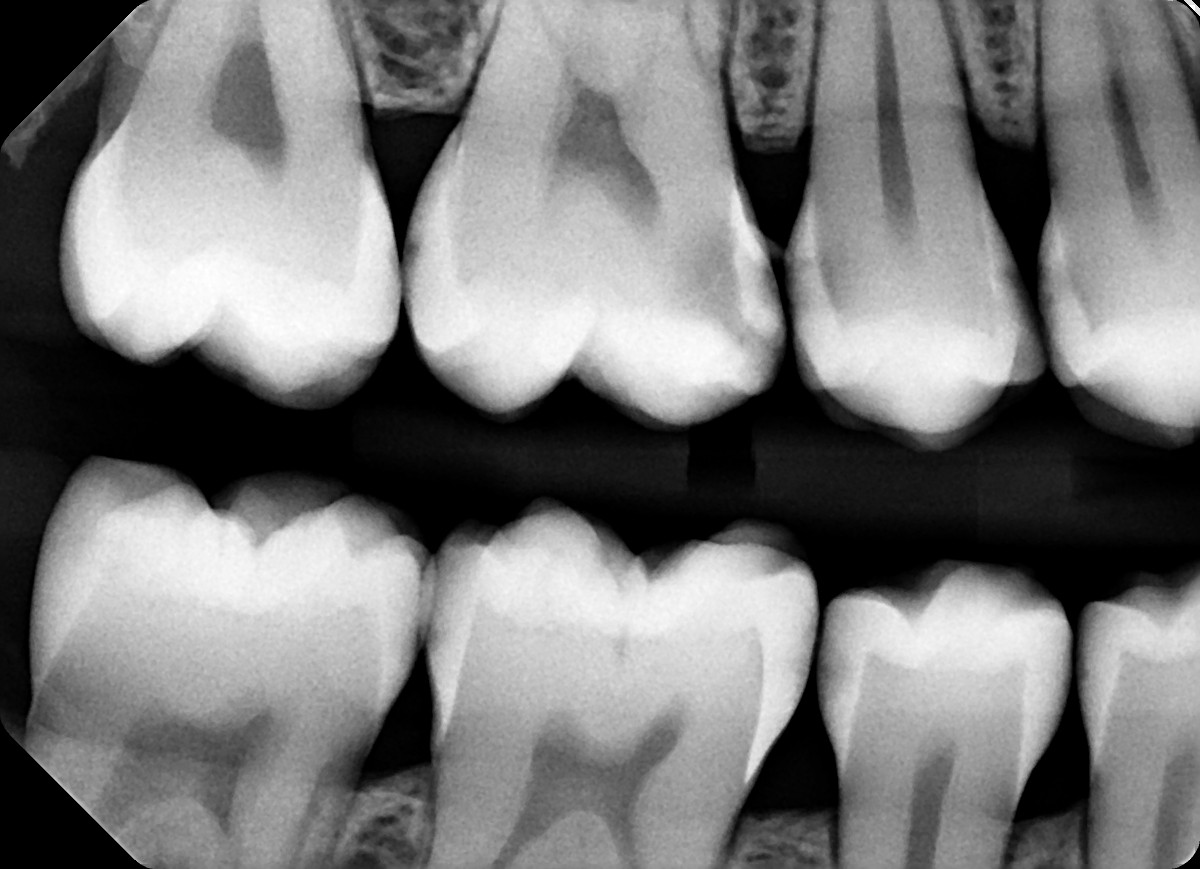

1.  In the X ray bellow for which jaw periodontal bone loss is evident?